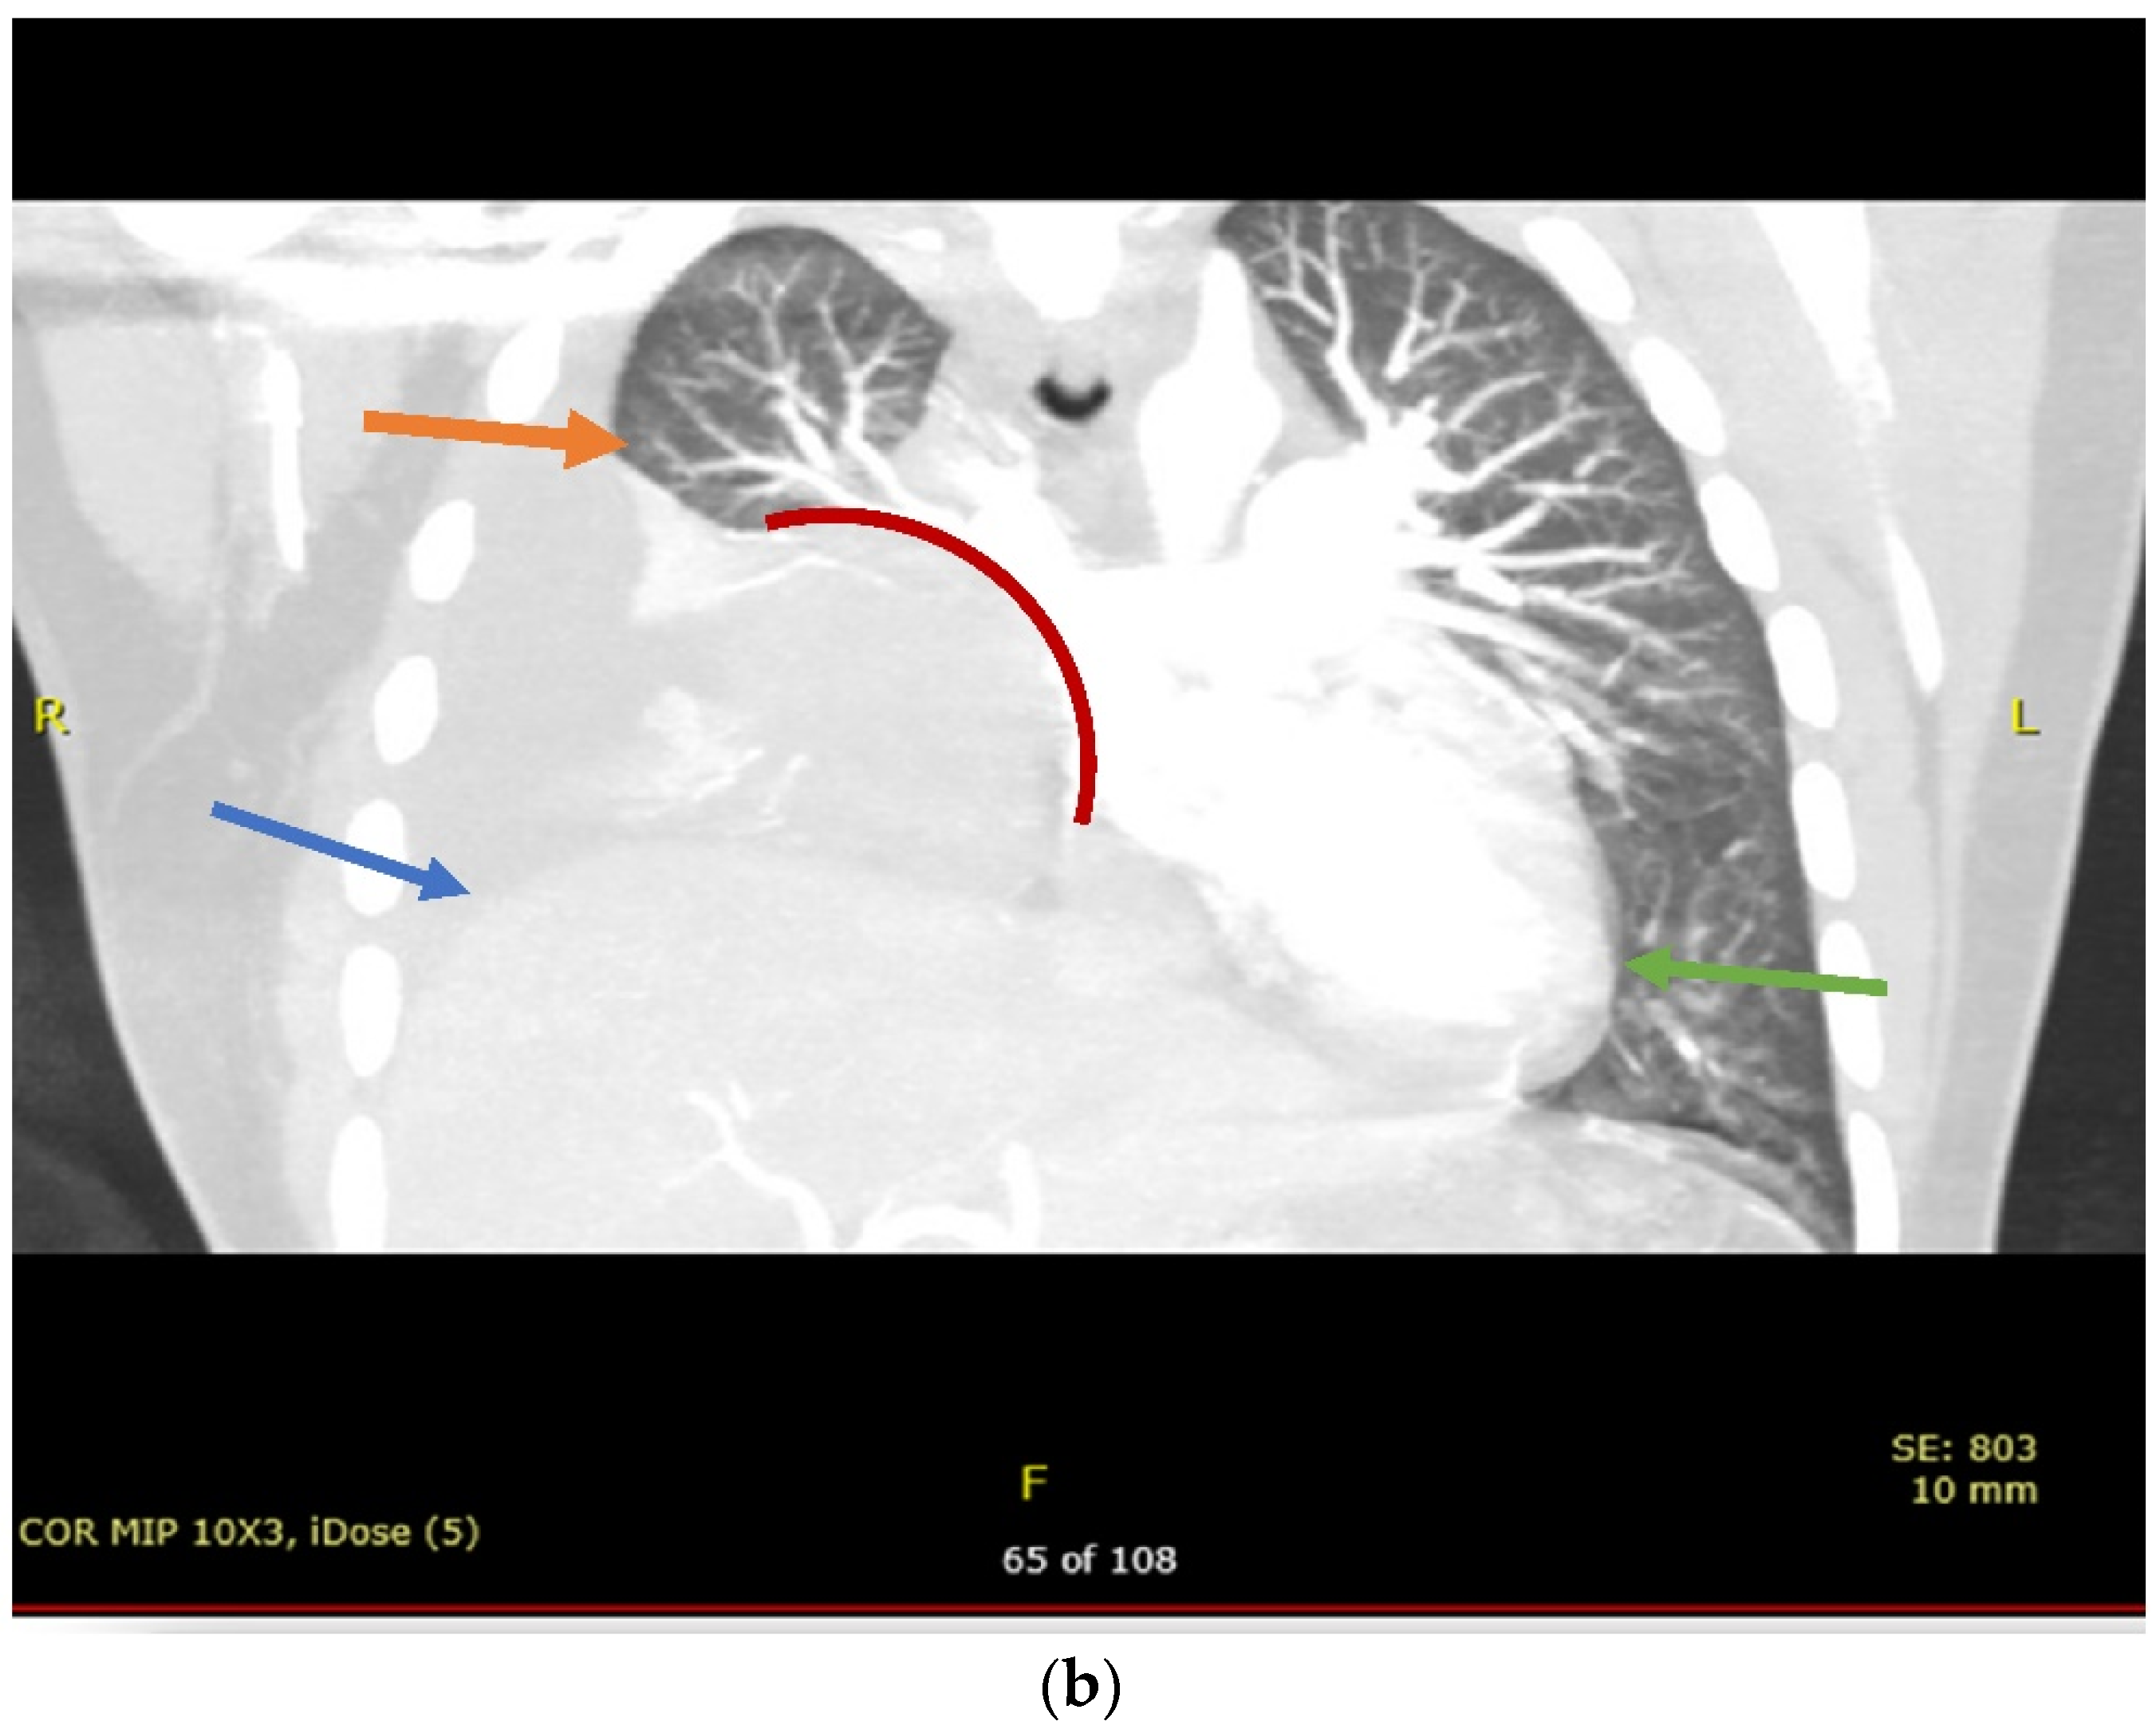

2. Case Presentation